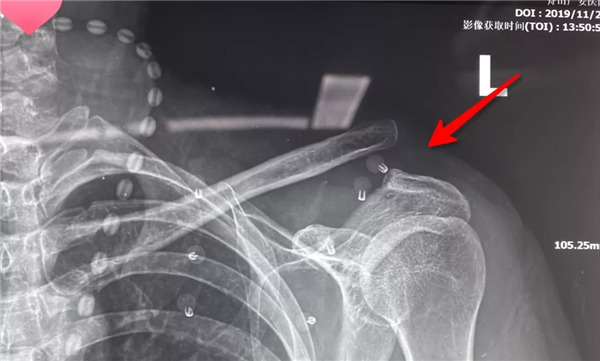

術(shù)前拍片--患者的肩鎖關(guān)節(jié)脫位屬于Rockwood  5型脫位

由于楊女士肩鎖關(guān)節(jié)脫位屬于Rockwood 5型脫位,廣安醫(yī)院危立軍副院長(zhǎng)會(huì)診后建議楊女士的肩鎖關(guān)節(jié)脫位進(jìn)行手術(shù)復(fù)位固定。